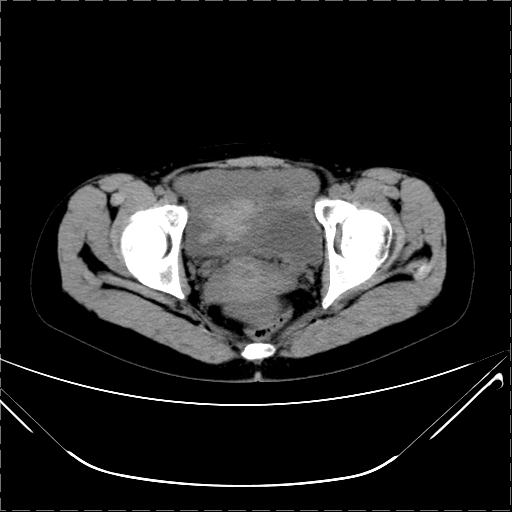

女 29岁 突然腹部疼痛1天 b超示子宫左后方肿块。月经正常。

请各位指教 该病人子宫周围云絮状高密度影是什么

影像表现复杂,膀胱上见一囊性包块,比膀胱密度高,其内有不均匀稍高密度,似与道格拉斯窝肿物无分界,病灶没有张力,因其腹平坦,推定其具有流动性,但又似见包膜,而b超没有报告这一现象。确实没见过。考虑卵巢囊肿蒂扭转并囊内出血可能。

病变主要位于道格拉斯窝,而且大体形态比较扁平且贴合子宫直肠,无明显张力及对周围脏器压迫,所以考虑为液体,而中间可见囊样病变伴环形强化,期内还可见分隔影,结合突发急性腹痛故多考虑囊腺瘤伴破裂出血。

腹腔镜术后 卵巢黄体囊肿破裂出血